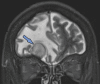

Neurodegenerative diseases are a devastating group of disorders that can be difficult to accurately diagnose. Although these disorders are difficult to manage owing to relatively limited treatment options, an early and correct diagnosis can help with managing symptoms and coping with the later stages of these disease processes. Both anatomic structural imaging and physiologic molecular imaging have evolved to a state in which these neurodegenerative processes can be identified relatively early with high accuracy. To determine the underlying disease, the radiologist should understand the different distributions and pathophysiologic processes involved. High-spatial-resolution MRI allows detection of subtle morphologic changes, as well as potential complications and alternate diagnoses, while molecular imaging allows visualization of altered function or abnormal increased or decreased concentration of disease-specific markers. These methodologies are complementary. Appropriate workup and interpretation of diagnostic studies require an integrated, multimodality, multidisciplinary approach. This article reviews the protocols and findings at MRI and nuclear medicine imaging, including with the use of flurodeoxyglucose, amyloid tracers, and dopaminergic transporter imaging (ioflupane). The pathophysiology of some of the major neurodegenerative processes and their clinical presentations are also reviewed; this information is critical to understand how these imaging modalities work, and it aids in the integration of clinical data to help synthesize a final diagnosis. Radiologists and nuclear medicine physicians aiming to include the evaluation of neurodegenerative diseases in their practice should be aware of and familiar with the multiple imaging modalities available and how using these modalities is essential in the multidisciplinary management of patients with neurodegenerative diseases.©RSNA, 2020.